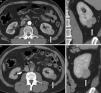

Nearness, cercanía (N)El componente N denota la cercanía del sector más profundo del tumor al sistema excretor o seno renal. Esto es relevante para evaluar la resecabilidad del tumor y la necesidad de realizar reconstrucciones complejas. Si la distancia de la parte más cercana del tumor al sistema excretor o seno renal es igual o mayor de 7mm, se asigna un punto; mientras que si está entre 4 y 7mm, se le otorgan dos puntos. Los tumores que se encuentran en contacto, invaden o están a 4mm o menos del sistema colector o seno renal suponen tres puntos.

Los valores de corte 4 y 7 fueron utilizados para simplificar la escala y asemejarla a la usada para la medición del radio tumoral. El análisis de esta medida se realiza mejor con imágenes en la fase excretora (figs. 6 y 7).

TCMC, en planos (a) axial, (b) coronal en fase excretora y (c) sagital en fase excretora, de un hombre de 67 años de edad con carcinoma de células renales, variedad papilar, de 6,2cm (flechas). La lesión se encuentra a más de 7mm del sistema colector o seno renal (línea roja). El N es igual a uno. RS: 2+1+1+p+1=5p (baja complejidad quirúrgica).

TCMC, en planos (a) axial, (b) coronal en fase excretora y (c) axial en fase excretora y (d) sagital, de un hombre de 43 años de edad con carcinoma de células claras de 6,3cm (flechas). La masa se encuentra a menos de 2mm del sistema colector o seno renal (esto es evaluado mejor en fase excretora). El N es igual a tres. RS: 2+2+3+p+2=9p (mediana complejidad quirúrgica).